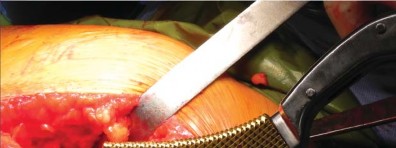

يتم عمل شق مائل من الخلف القريب إلى الأمام البعيد، يتمركز فوق طرف المدور الكبير، ويبلغ طوله حوالي 10-12 سم للرجل متوسط الوزن (70 كجم). يتم تقليل تشريح تحت الجلد لتحديد اللفافة الأساسية إلى الحد الأدنى لمنع تكوين مساحة ميتة.

إدارة الأنسجة الرخوة وخلع رأس الفخذ

تُشق اللفافة العريضة والألياف الأمامية للعضلة الألوية الكبرى التي تتصل باللفافة العريضة قريبًا باستخدام الكي الكهربائي بما يتماشى مع شق الجلد. يتم إزاحة الجراب المدوري خلفيًا للمساعدة في رؤية العضلة الألوية الوسطى والعضلة المتسعة الجانبية. يتم رفع الجزء الأمامي من العضلة الألوية الوسطى عن المدور الكبير باستخدام الكي الكهربائي، ثم يتم تشريحه بشكل غير حاد بما يتماشى مع أليافه بزاوية 45 درجة أمامية-قريبة عند تقاطع الثلثين الأوسط والأمامي للعضلة. يقتصر التشريح على أقل من 3-4 سم باتجاه الرأس من طرف المدور الكبير لتجنب إصابة العصب الألوي العلوي. في غلاف مستمر مع العضلة الألوية الوسطى، يتم رفع الجزء الأمامي من العضلة المتسعة الجانبية عن حافة العضلة المتسعة ويتم شقه بعيدًا بين ثلثيه الأوسط والأمامي. يتم وضع مبعد هومان غير حاد في شق العضلة الألوية الوسطى لسحب الألياف الخلفية وكشف طبقة من الدهون بين المستويات الألوية. تُشق الكبسولة خلف العضلة الألوية الصغرى وعلى طول الجانب العلوي من عنق الفخذ. يقوم المساعد بتباعد وثني وتدوير الطرف خارجيًا لخلع رأس الفخذ.

تحضير الفخذ والحق

يتم تحديد مستوى قطع عنق الفخذ مسبقًا بالتخطيط (باستخدام الأشعة السينية) ومواءمته أثناء الجراحة مع المدور الكبير. بعد قطع عنق الفخذ، يتم تحضير الحُق بالطريقة القياسية قبل تحضير الفخذ. يفضل الأستاذ الدكتور محمد هطيف عادةً وضع الكأس وفقًا للمعالم التشريحية لإعادة إنشاء التوجيه الطبيعي للحُق لدى المريض ويتحقق من الإصدار والميل الصحيحين عن طريق الجس والرؤية المباش